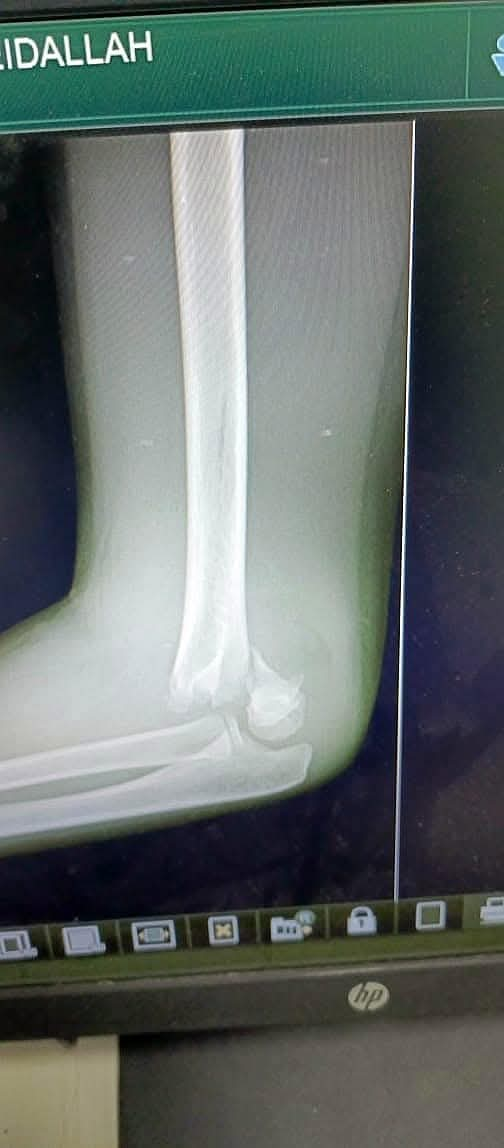

وطنا اليوم -  يقوم بعمليات تثبيت الكسور المعقدة بشكل طاريء وتبديل المفاصل بشكل مبرمج  مما خفف على المواطنين البحث عن أسرة في مستشفيات مركزية رغم صعوبة عمليات العظام من الناحية التقنية في المستشفيات النائية  إضافة الى  استقبال اعداد كبيرة بالعيادات ومعالجة جميع المرضى بالطرق المثلى انه الدكتور الانسان البارع والمتميز يزيد البريزات طبيب العظام في مستشفى الاميرة سلمى / ذيبان عيادة العظام  علماً بأنه كان  مستشفى تحويلي منذ تاسيسه والدكتور البربزات وقبل اربع سنوات في عام 2020  منذ انتقاله للمستشفى يقوم بهذه العمليات ومن بينها  عمليات نوعية لمرضى يعانون من كسور معقدة في الترقوة واجراء عمليات دقيقة ومعقدة لكسور لمرضى في مختلف أنحاء الجسم وعمليات تثبيت الكسور المعقدة وتركيب المفاصل وغيرها الكثير  والديسك " وآلامه وتبعاته وعلاجه وإجراء عمليات معقده وصعبه.

وأجرى الدكتور البريزات عمليات كبرى في جراحة العظام والتي تحتاج إلى مراكز متقدمة ومتطورة. وكذلك العمل على تثبيت أغلب انواع الكسور بطريقة طارئة وتبديل المفاصل بطريقة مبرمجة بما يتناسب مع امكانات المستشفى والتي هي  جزء من  العمليات الدورية بمستشفى الاميرة سلمى في ذيبان  والتي تخفف العبئ على المستشفيات المركزية وعلى المواطن في آن واحد.